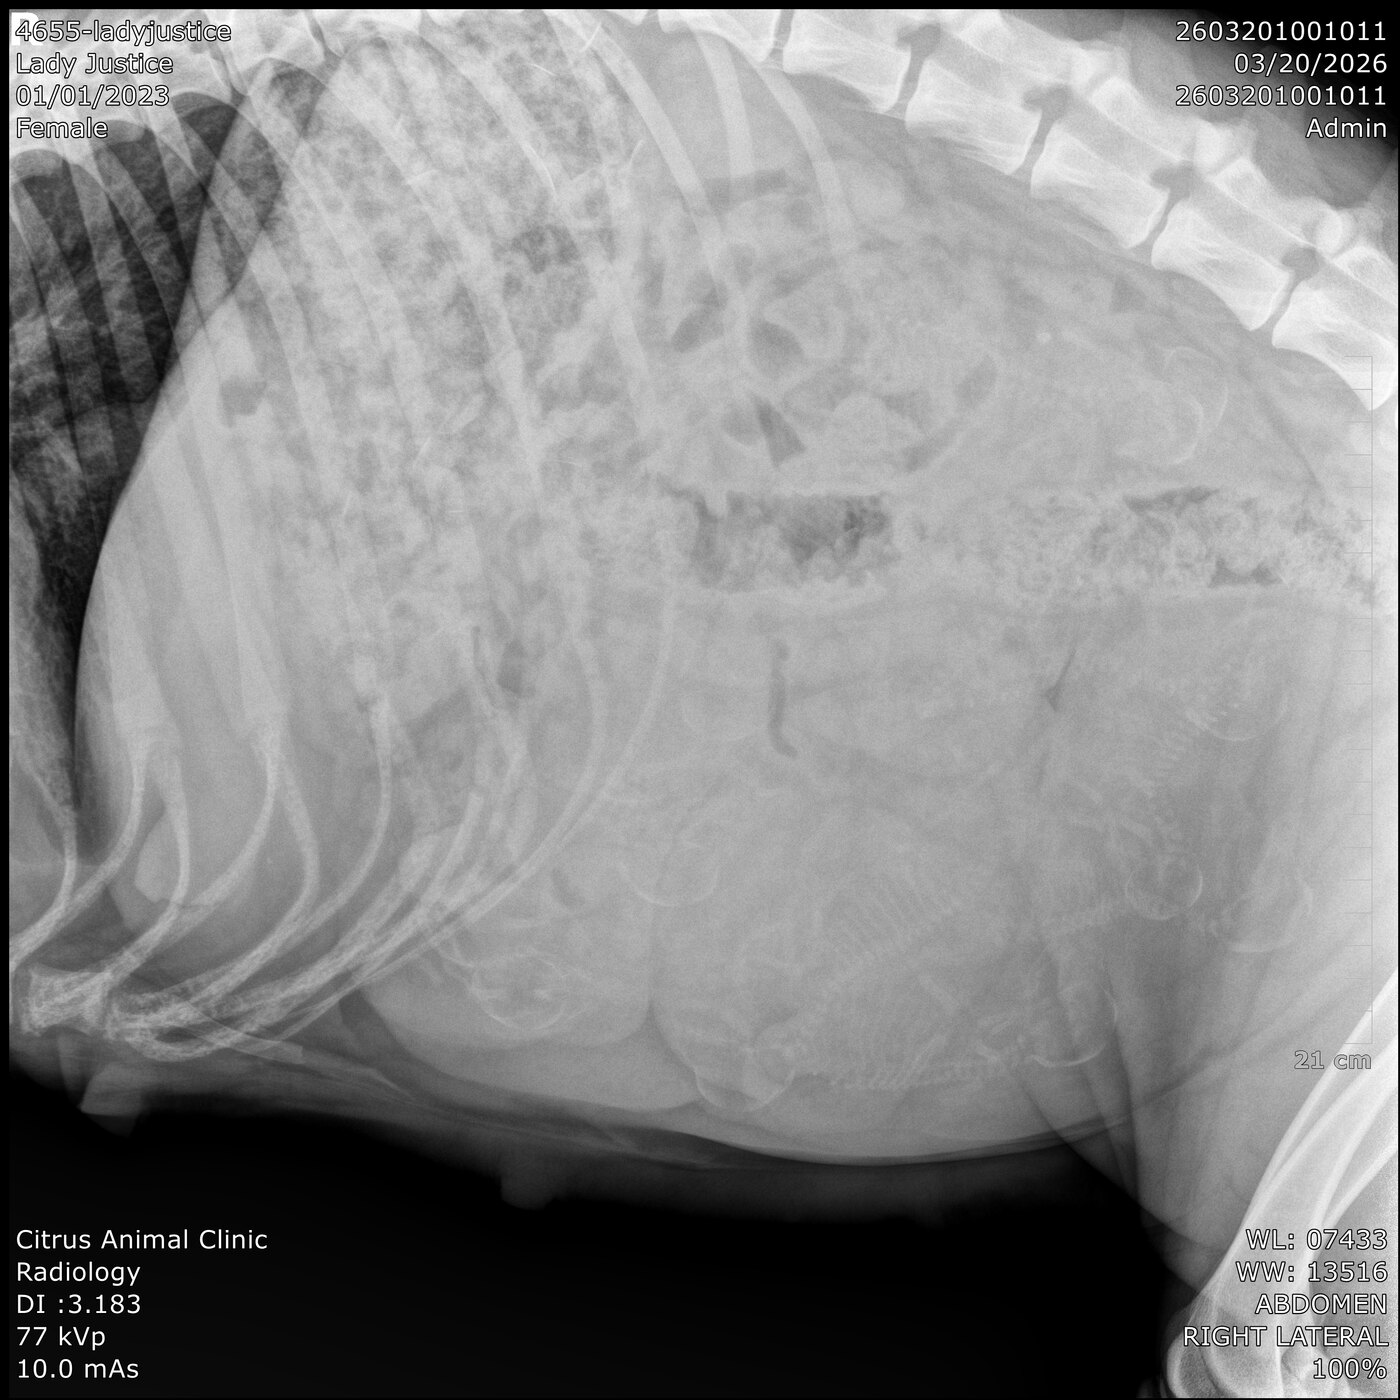

Breeding date 1/30/26. Confirmation date 3/16/26. Due date tenatively 4/3/26. 11 pup litter count confirmed by vet.